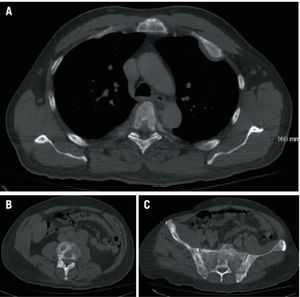

A 39-year-old Hispanic male presented with complaints of mucous stools, loss of appetite, rectal bleeding and a 30-pound weight loss within the past several months.